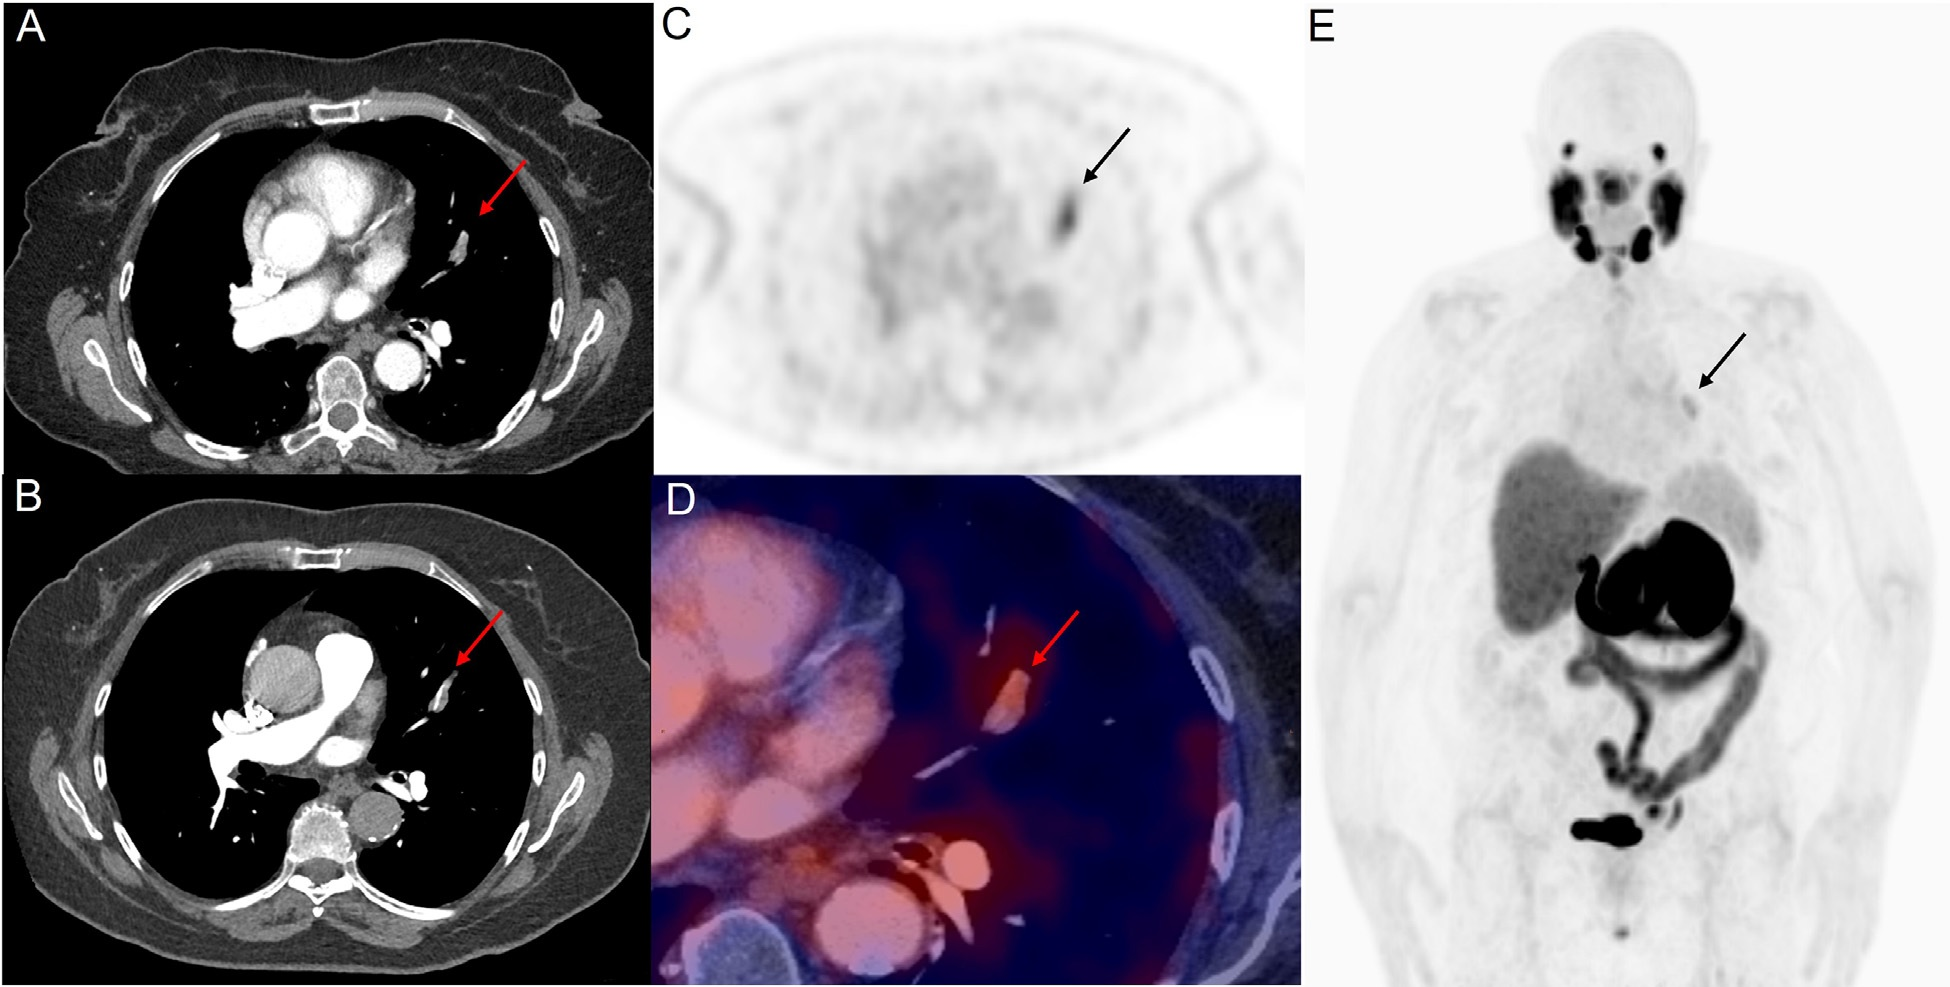

Пэт псма что это

Пэт псма что это 104 фотографий